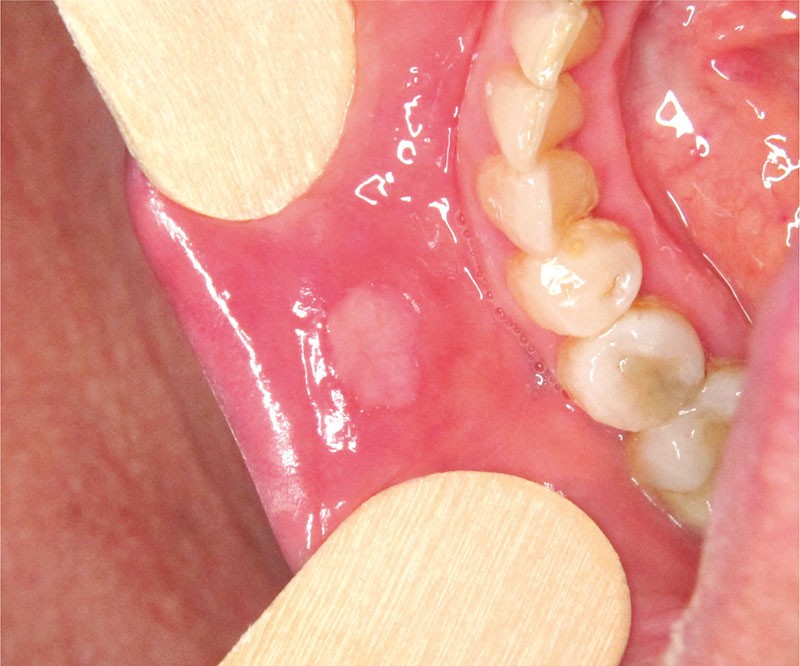

Un patient de 12 ans sans antécédent médical, a consulté pour des aphtes depuis 3 ans. Il décrivait une poussée tous les 15 jours. Les lésions avaient une durée d’une dizaine de jours et ont toujours été localisées sur la muqueuse buccale. Il ne relatait aucun épisode d’hyperthermie au cours des poussées et ne présentait pas d’altération de l’état général. Son développement staturo-pondéral était dans la moyenne. L’utilisation de topiques (bains de bouche à la chlorhexidine, acide hyaluronique) n’a rien changé. L’examen clinique révélait une ulcération de la partie muqueuse de la lèvre inférieure. Cette ulcération mesurait moins de 1 cm de diamètre. Elle était entourée d’un liseré érythémateux. La palpation de la lésion ne révélait pas d’induration. La palpation des aires ganglionnaires cervico-faciales ne révélait pas d’adénopathie.

L’hypothèse d’une aphtose est la plus probable compte tenu que l’ulcération est compatible avec un aphte (ulcération et érythème périphérique, cicatrisation en une dizaine de jours, localisation sur la muqueuse non kératinisée).